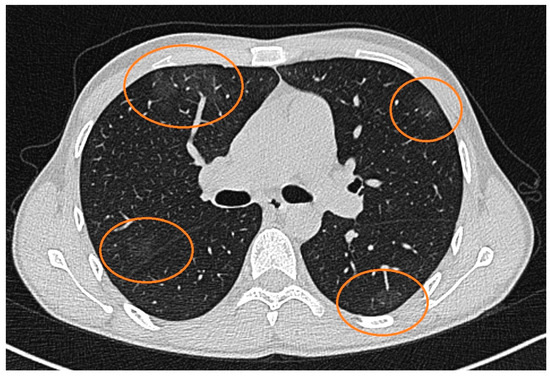

Figure 2.

CT scan of the chest showing axial cross-sectional images of the lungs with multiple areas marked in orange circles. These marked areas represent ground-glass opacities. The opacities are distributed in both lungs and subpleural zones, suggesting a diffuse, bilateral pattern. The findings indicate a mild form of SARS-CoV-2 infection, with all lung lobes being affected.